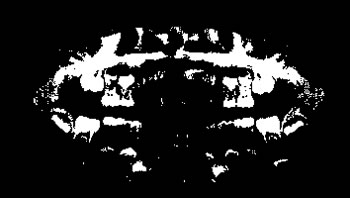

Refer to caption

Determining ROI

For each image, after the annotation of the teeth, the buccal region was also annotated, covering the whole region delineated by the contour of the jaws. This process was carried out in view of preserving the area containing all the teeth (objects of interest). Finally, the region of interest (ROI) was determined by multiplying the values of the pixel array elements, representing the original panoramic X-ray image, by its corresponding binary matrix, resulting from the process of oral annotation. Figure 5 illustrates the whole process to determine the ROI of the images.